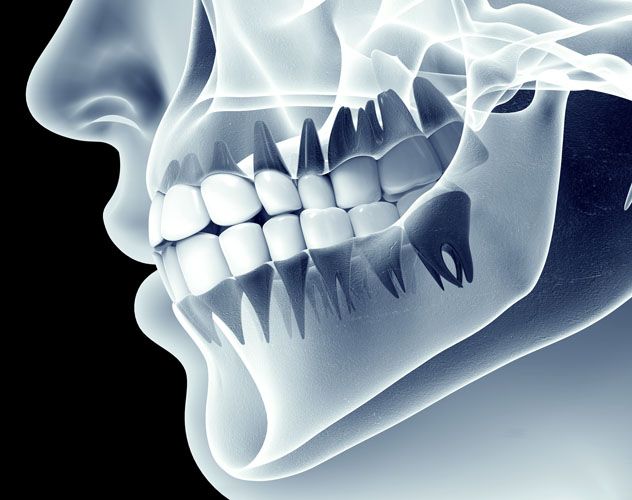

Dental Implants: The Best Choice

Over the past 10 years, the popularity of Dental Implants has absolutely taken off.  There are many reasons for this, however, I believe the main reason lies in their versatility and predictability.Dental implants are titanium tooth replacements which are placed into the jaw.  They are very similar in shape and size to the actual tooth roots they replace.  The procedure to place them is surprisingly comfortable, with the use of only local anesthesia, and very often the whole procedure takes about as long as a typical filling.  The advent of  Dental CAT...